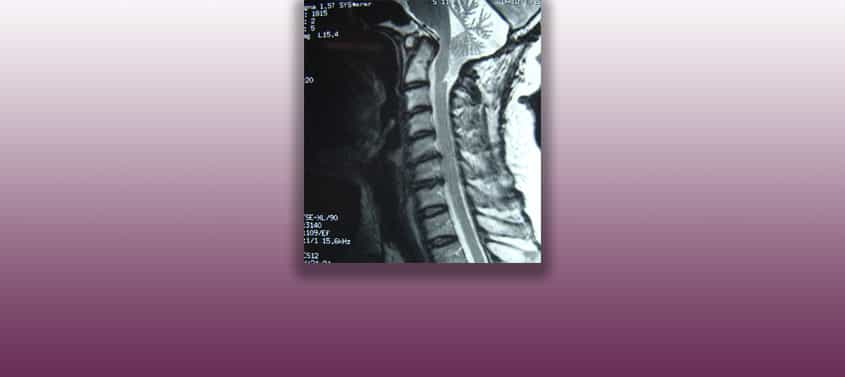

Hirnstammkinking oder -abwinklung

Last update: 17/10/2023, Dr. med. Miguel B. Royo Salvador, Arztnummer: 10389. Neurochirurg und Neurologe. Definition Beim Hirnstammkinking (knickung) oder Hirnstammabwinklung handelt es sich um einen nach vorne projizierten Winkel des Hirnstamms, der zwischen dem Pons und dem Rückenmark entsteht. Diese Strukturen (Pons und Rückenmark) neigen dazu, auf der bulbomedullären Ebene einen Winkel zu bilden. Eine […]